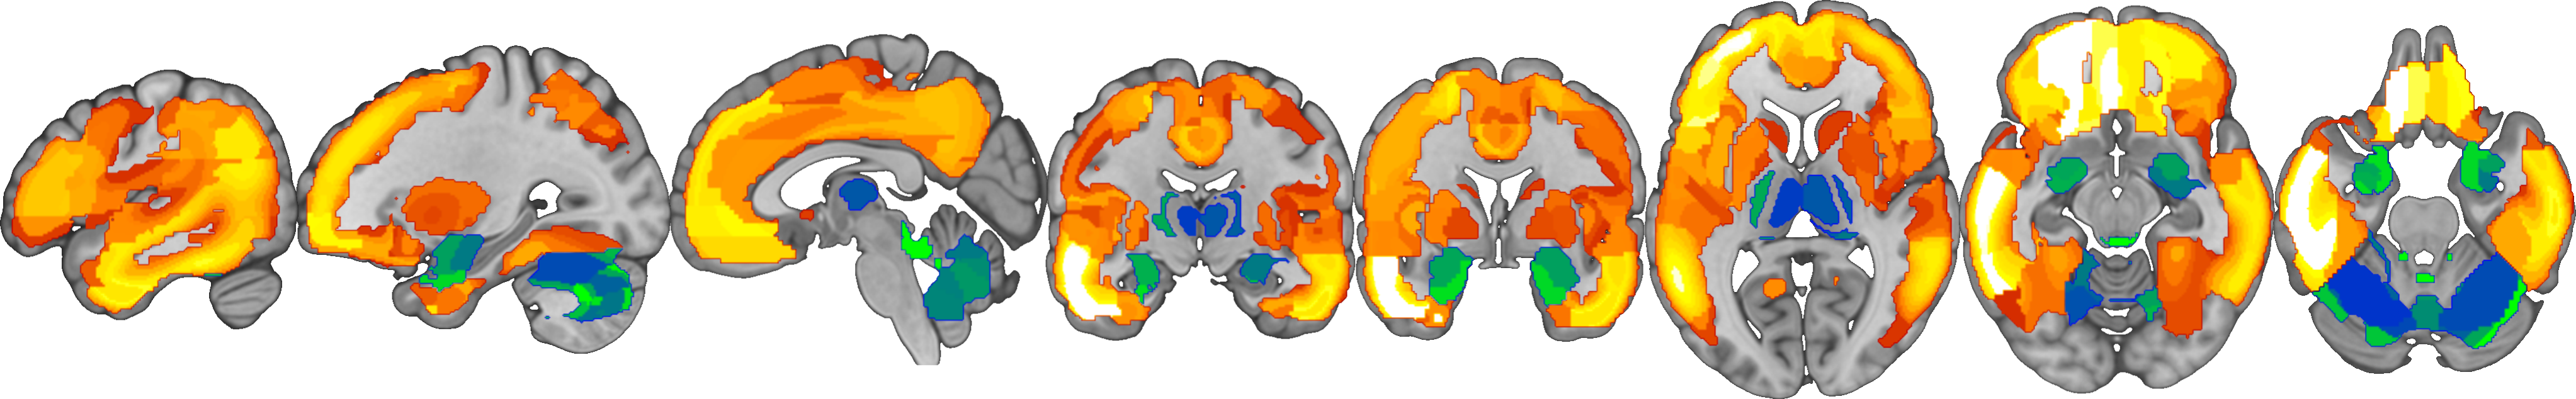

- Visualizes the cluster-specific posterior distributions